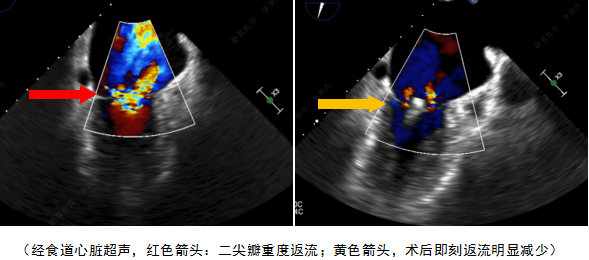

5月16日上午,中南大学湘雅二医院周胜华教授团队成功使用国内自主研发的经导管二尖瓣瓣膜夹系统(德晋医疗DragonFly™)为一位高龄患者完成了经导管二尖瓣修复手术。医院成为该产品多中心临床研究项目启动后完成手术的第二家中心。手术由方臻飞教授担任第一术者,浙江大学附属第二医院王建安、刘先宝、蒲朝霞三位教授现场指导,美国弗吉尼亚大学David Scott Lim教授和香港亚心医院林逸贤教授线上讨论与指导,团队配合默契,不到3小时顺利完成手术。术后,患者二尖瓣返流即刻消失、左房压力较前明显下降;术后患者拔除气管插管,恢复良好。经导管二尖瓣修复术的开展,标志着继2015年开展经导管主动脉瓣置换术(TAVR)后,中南大学湘雅二医院心脏瓣膜病的介入治疗水平进一步与国际接轨。

该患者是一名70岁老人,活动后胸闷反复6月余入院。入院诊断为二尖瓣脱垂伴腱索断裂并关闭不全,超声心动图提示二尖瓣脱垂(P2)伴腱索断裂并关闭不全(重度)。心脏团队评估患者开胸手术风险较高,微创二尖瓣修复手术是最适合的治疗方式。